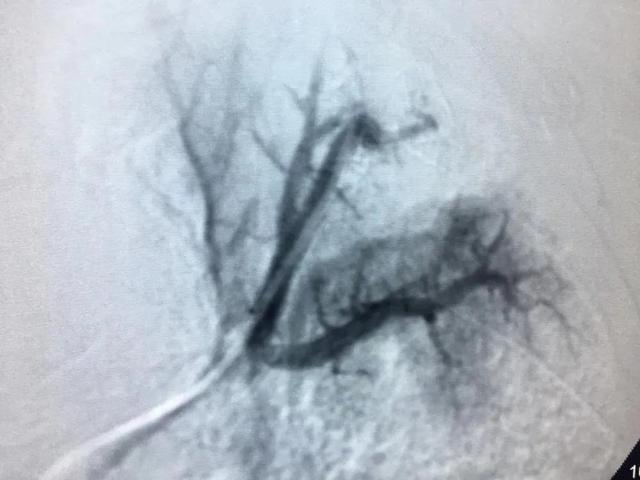

手术进行了2个小时,术中造影可见患者左、右支气管动脉、隔动脉、肋间动脉等多支血管异常增粗、迂曲、远端可见出血病灶;左上肺动脉分支末端见假性动脉瘤,是出血的“罪犯血管”,即行支气管动脉栓塞和肺动脉假性动脉瘤栓塞术。术后患者咯血停止,无并发症及不良反应发生,手术获得了满意的效果。